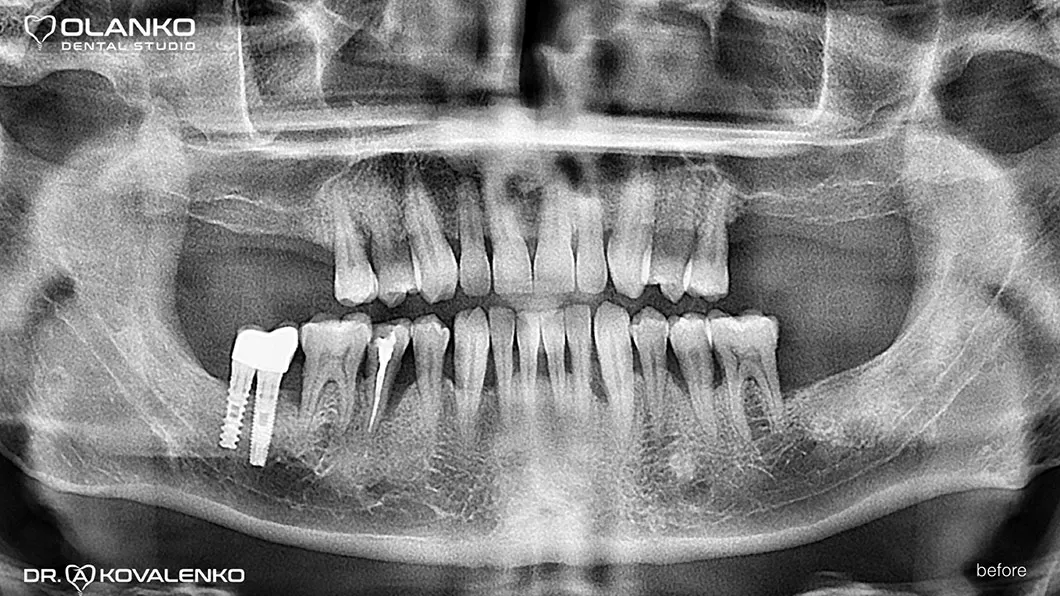

Пацієнт звернувся зі скаргами на відсутність жувальної групи зубів.

Лікування: операція кісткової пластики на верхній щелепі (двосторонній синус-ліфтинг). Установка 4-х зубних імплантатів на верхній щелепі і один зубний імплантат на нижній щелепі. Пластика м'яких тканин в області імплантатів.

Ситуація до